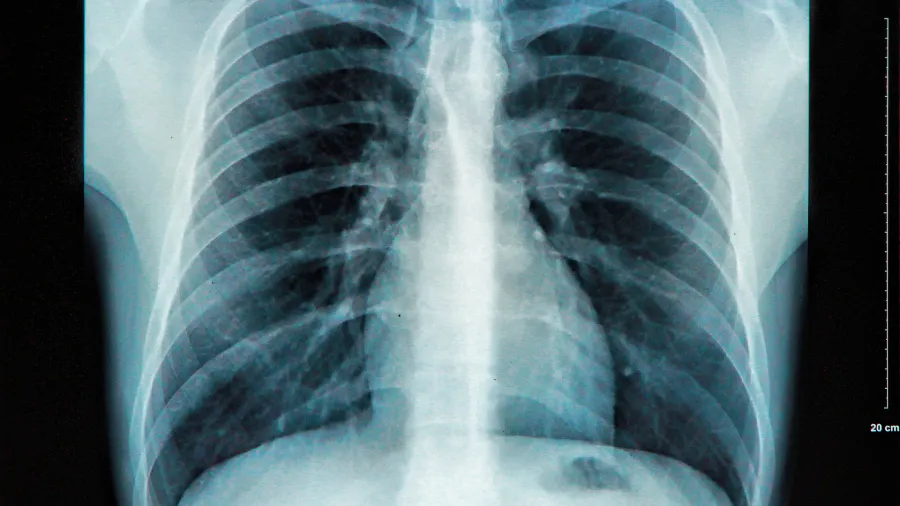

X-ışınlarının Keşfi (1895): Wilhelm Conrad Roentgen tarafından yapılan X-ışınları keşfi, tanısal tıbbı dönüştürerek doktorların cerrahi yapmadan insan vücudunun içini görmelerini sağladı.